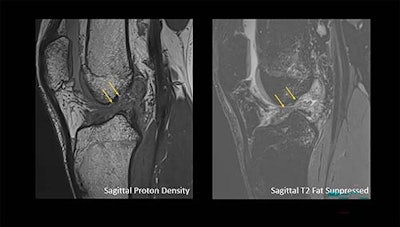

Arrows show a complete anterior cruciate ligament rupture in an 18-year-old male who had a knee injury while playing football.RSNA